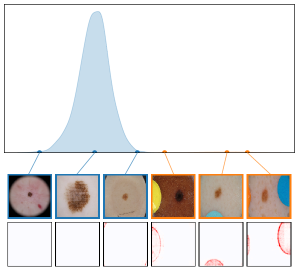

Both input and latent relevance clustering require subsequent human supervision to determine whether outlier clusters represent valid or spurious behavior. To semi-automate this process, Anders et al. [3] propose using Fisher Discriminant Analysis [37] to rank class-wise clusterings by linear separability, while Dreyer et al. [27] computes similarities between prototypes. The results of clustering approaches can serve as an initial set for bias modeling methods outlined in Sec. 3.2, which can be refined iteratively. An example outlier cluster of latent relevances is shown in Fig. 4 (top), with all samples containing the spurious band-aid concept.

where reduces the dimension to , and the pairwise distance function is applied along all channel dimensions in the latent representation , either given by activations or relevance scores for layer . Note that this approach assumes over-parameterization resulting in redundant neurons, allowing to distinguish between similar and dissimilar concept representations. An example is shown in Fig. 4 (bottom), where latent relevance scores from a ResNet50 model trained for melanoma detection are used to identify outlier concepts, specifically a cluster focusing on band-aids rather than clinically relevant features. Notably, Eq. 3 can easily be extended to find outlier directions instead of neurons. Specifically, this involves a linear transformation of latent representations using the directions of interest, e.g., obtained in unsupervised manner as described in Sec. 3.1.

We further plot the distribution of CAV-based bias scores for biased and clean samples for the real-world artifacts ruler (ISIC2019) and pacemaker (CheXpert) in Fig. 8. We compute bias scores using the best performing CAV per artifact and use latent activations after the residual block of the ResNet50 model for ruler, and the convolutional layer of the VGG16 model for pacemaker. We show samples corresponding to the bias score in the top-1 and -99 percentiles of each set. Samples near the decision boundary are particularly interesting, as they may arise from labeling errors. Both examples demonstrate the retrieval of unlabeled artifact samples. The distributions of bias scores for additional artifacts are shown in Appendix A.6.2.